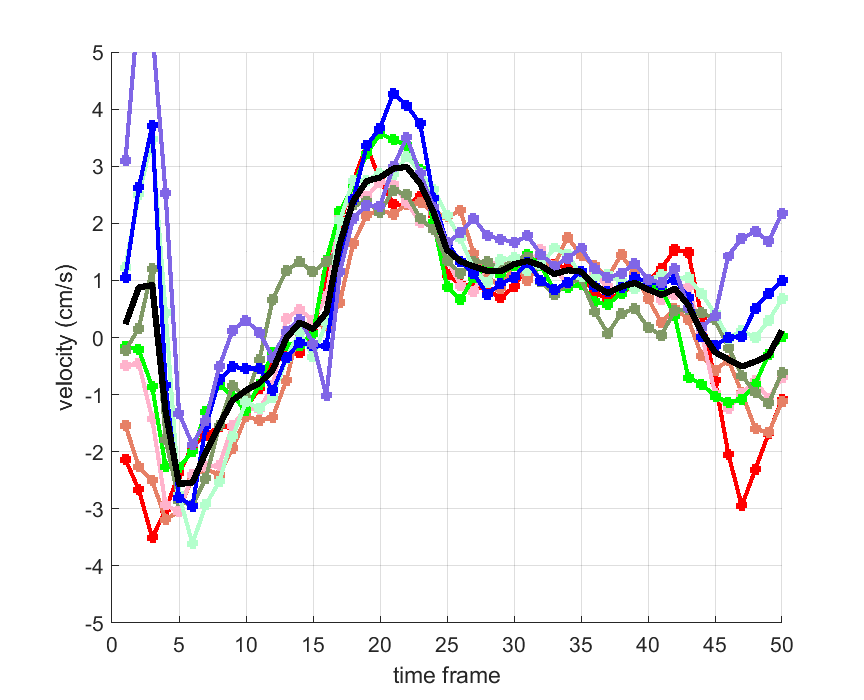

Time courses of the estimated translational component per subject, frame, slice and volume along the 3 velocity directions x, y and z are presented in Fig.6 - Fig.8.